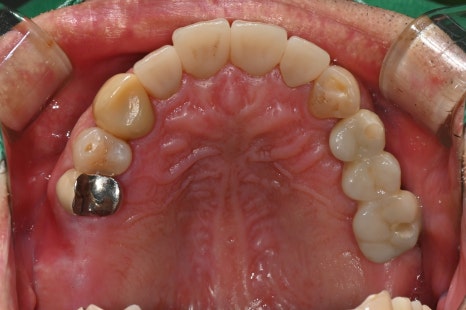

🖼️ Scene from the start of implant surgery

X-ray immediately after implant surgery and the intraoral view after surgery

🖼️ Completed molar implant prosthesis photo

Pre-designed implant prosthesis based on a digital scan / The actual intraoral setting